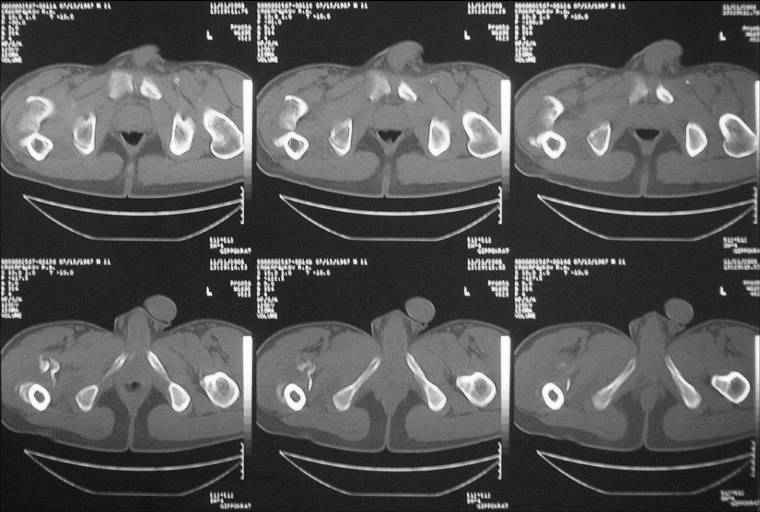

Уважаемые коллеги! Нужен совет. Больной Х., 21 год, ДЗ: ложный сустав вертельной области правого бедра.

Травма 8 мес. назад, ДТП, получил закрытый межвертельный перелом правого бедра. Лечился в городской больнице одного из городов-спутников г. Караганды скелетным вытяжением в течение 3 недель, затем кокситной гипсовой повязкой 2 мес. В настоящее время имеется укорочение конечности на 7 см, умеренная боль в вертельной области; ходит без костылей, полностью нагружая больную конечность, при нагрузке отмечается смещение дистального отломка проксимально примерно на 1,0 см.; объем движений в коленном суставе сохранен; при пальпации отломков боли нет, умеренная патологическая подвижность. Планируем внеочаговый остеосинтез спице-стержневым аппаратом, дистракция до восстановления длины бедра, вторым этапом остеосинтез стержнем Гамма. Есть надежда, что на дистракции пойдет сращение и у больного хватит терпения завершить лечение в аппарате.